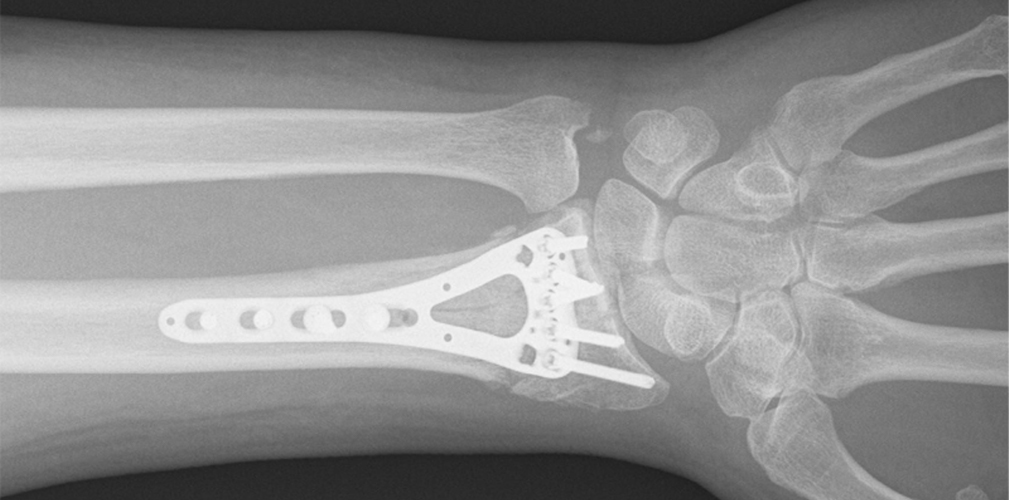

Possiamo dire che se l’hanno operato è sicuramente una frattura scomposta che necessitava di un intervento chirurgico. C’è da dire che negli atleti di alto livello spesso e volentieri succede che se c’è il dubbio di operare o meno si cerca di effettuare l’intervento chirurgico e avere quindi una certezza di un recupero magari migliore e in tempi più brevi. Mettendo una placca, il recupero e la calcificazione ossea avviene meglio e prima.

Ridurre e stabilizzare la frattura. Di solito viene posizionata una placca che si salda con delle viti che devono garantire la stabilità della frattura. Questa stabilità velocizza anche il callo osseo. Il velocizzare il callo osseo, ci permette di ottimizzare la ripresa. Dopo l’intervento vieni immobilizzato mettendo un gesso o in questo caso viene sostituito oggi da dei tutori termoplastici. Questo permette di far muovere le dita fin da subito all’atleta e non perdere quella parte di funzionalità che è importante tenere attiva.

Sono fratture che si possono risolvere nel giro di 5 o 6 settimane. A distanza di 15 giorni si fa una radiografia di controllo e si valuta che tutto vada bene. Si valuta se il tutore può essere già tolto per fare della fisioterapia antifiammatoria e passiva. Essendo un ciclista gli si può fare un tutore particolare per pedalare sui rulli già dopo una quindicina di giorni.

C’è un recupero effettivo. Più avanti ci sarà anche la possibilità di rimuovere la placca per evitare che in futuro crei fastidio al polso. Questo avviene di solito dopo un anno.